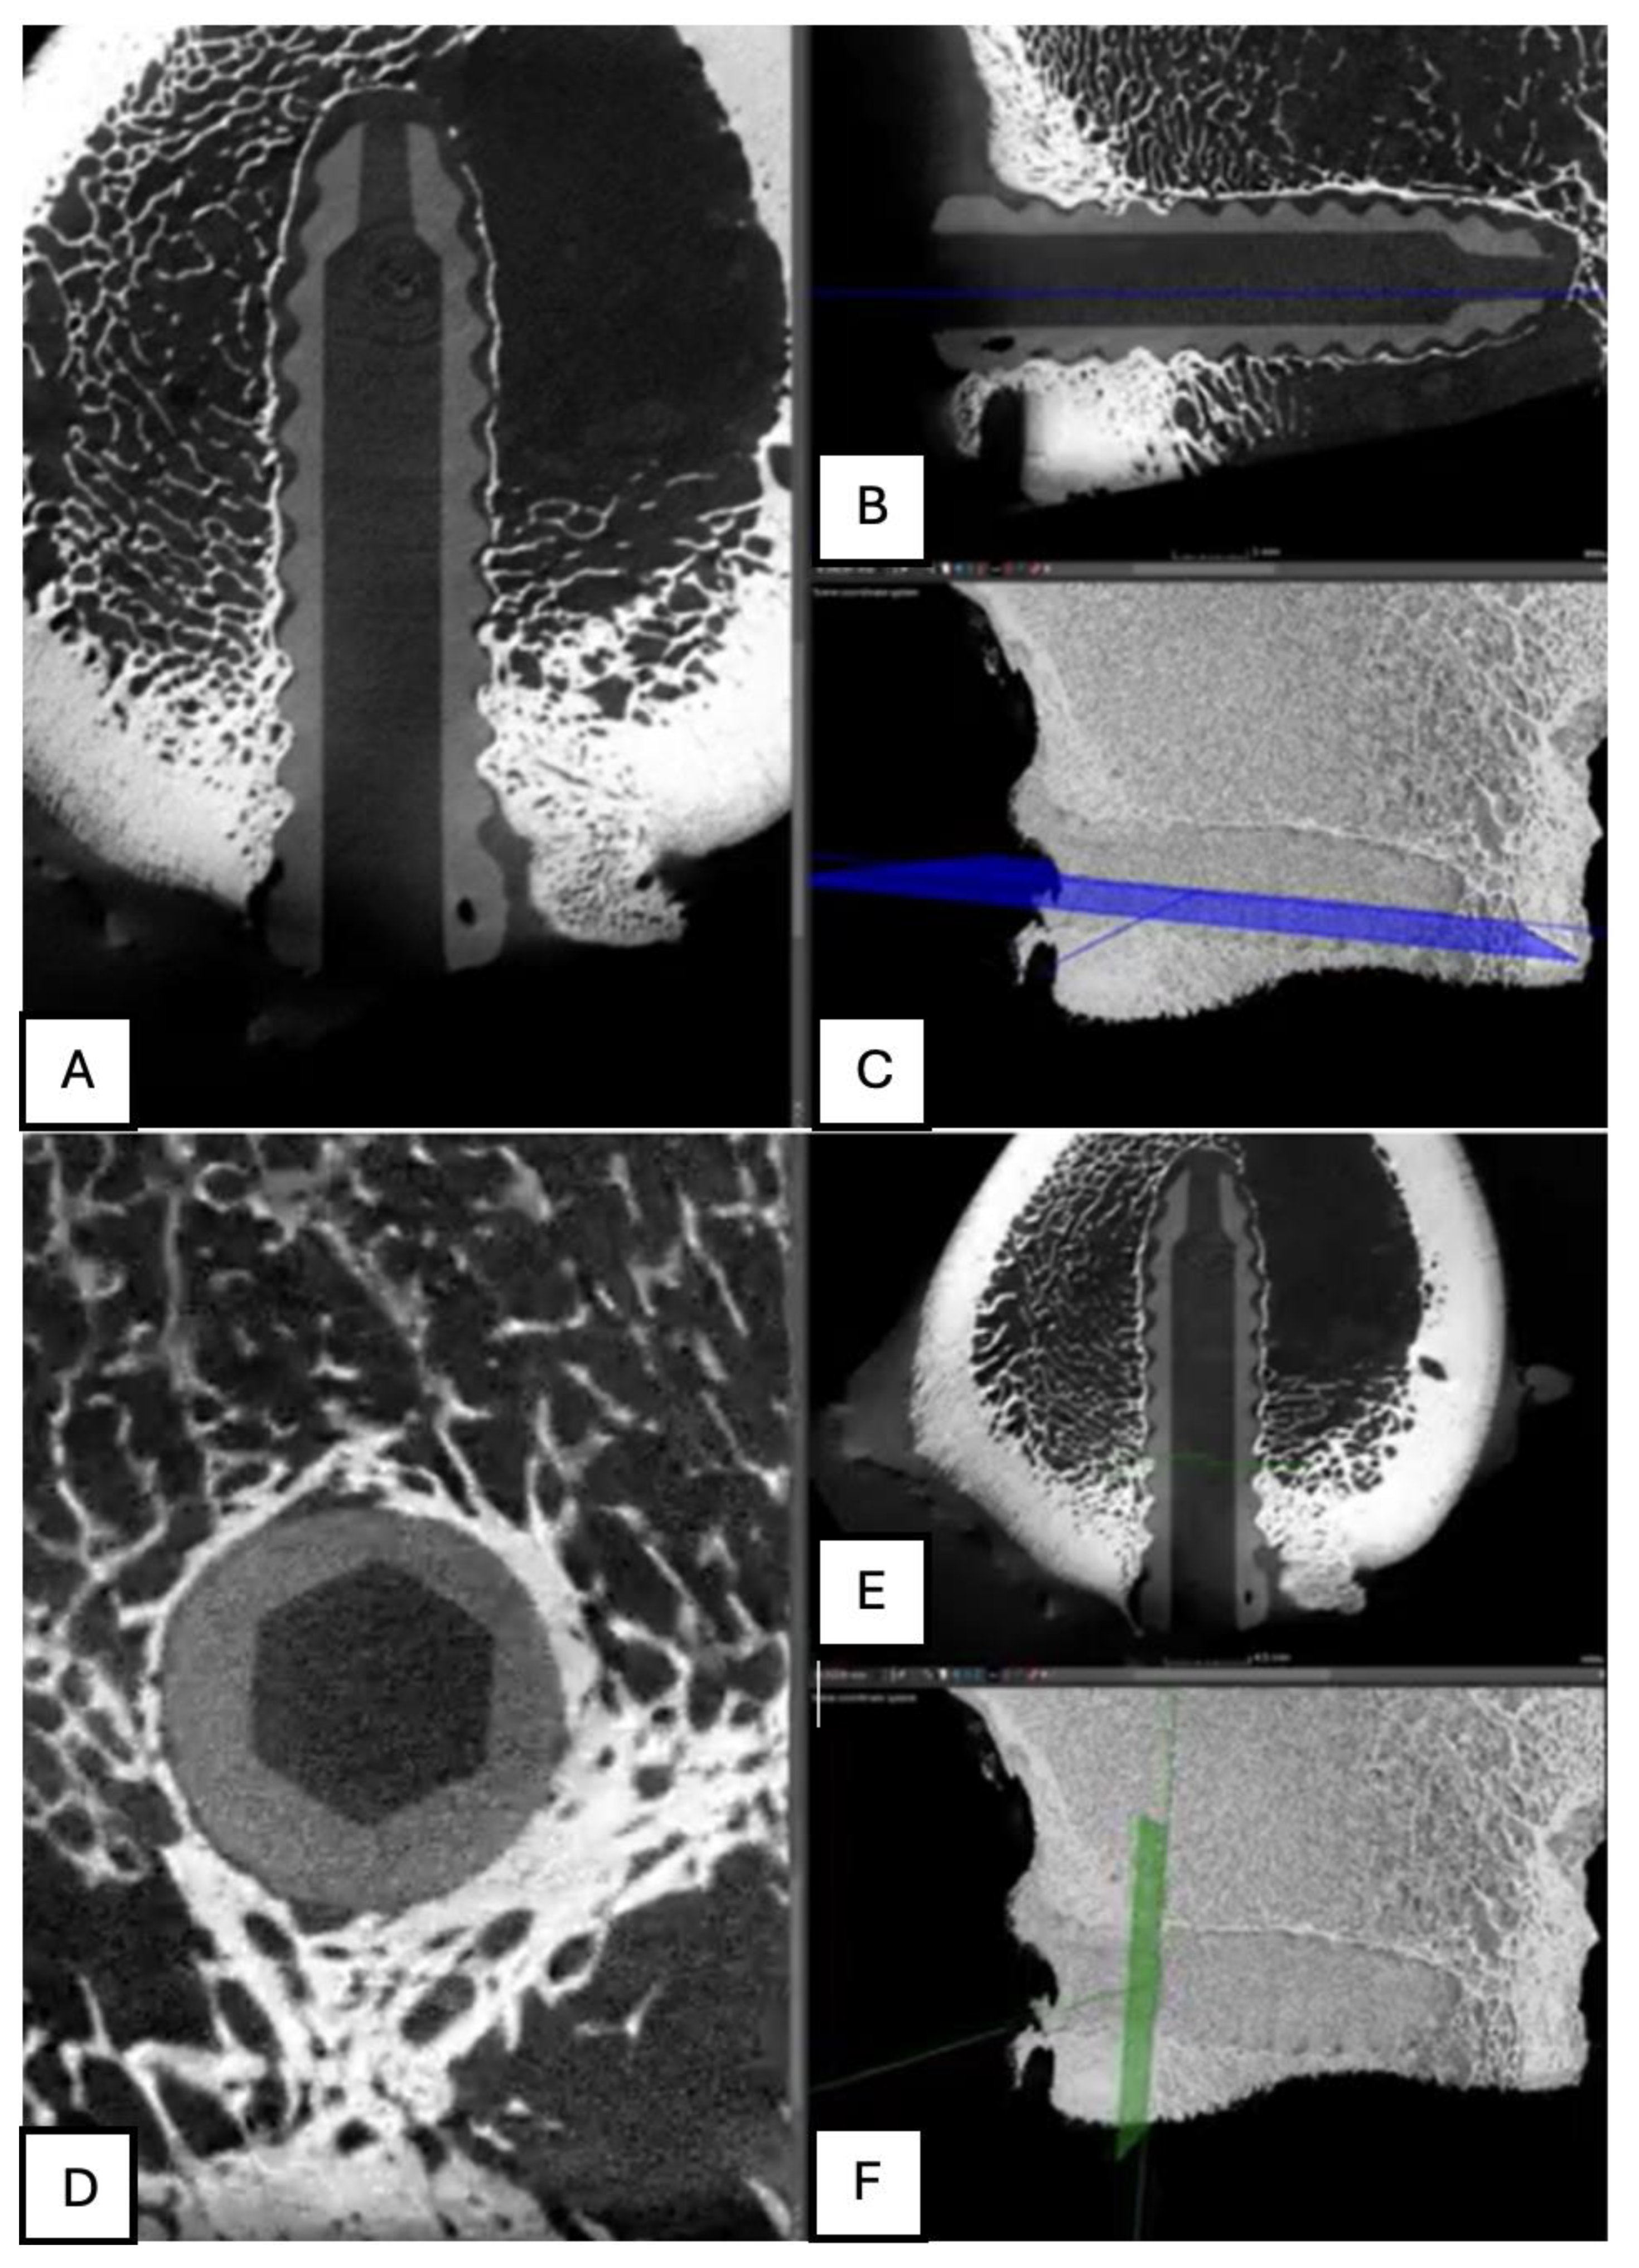

Figure 14. Computed tomography study (A) axial slice, (B,D,E,F) sagittal reconstruction, and (C) 3D visualisation of the left femur sample, one-month post-surgery, with PLDLLA material.

PLDLLA: In a 3D reconstruction view, the screw appears circumferentially, with a slight increase in bone density around it, suggesting initial bone growth that has not yet fully reached the implant. In the lateral view, slight bone growth is evident, with more development in the proximal third of the screw, indicating more pronounced consolidation in that area. Additionally, small hyperdensities within the screw suggest the presence of bone growth inside it. These findings reflect early progress in the osteogenic response and screw integration, although the consolidation process is still in its initial stages. (Figure 14)

Figure 20. Computed tomography study of the left femur sample, three-month post-surgery, with PLDLLA material. (A, F)Axial and (B,C,D,E) sagittal reconstruction.

PLDLLA: In a 3D reconstruction, the sagittal view reveals a circumferentially shaped screw. A hyperdense area is observed in the mid-third region of the screw, indicating ongoing bone growth. The lateral view confirms proper positioning of the screw within the femoral tunnel, occupying approximately 60% of the insertion tunnel. (Figure 20)